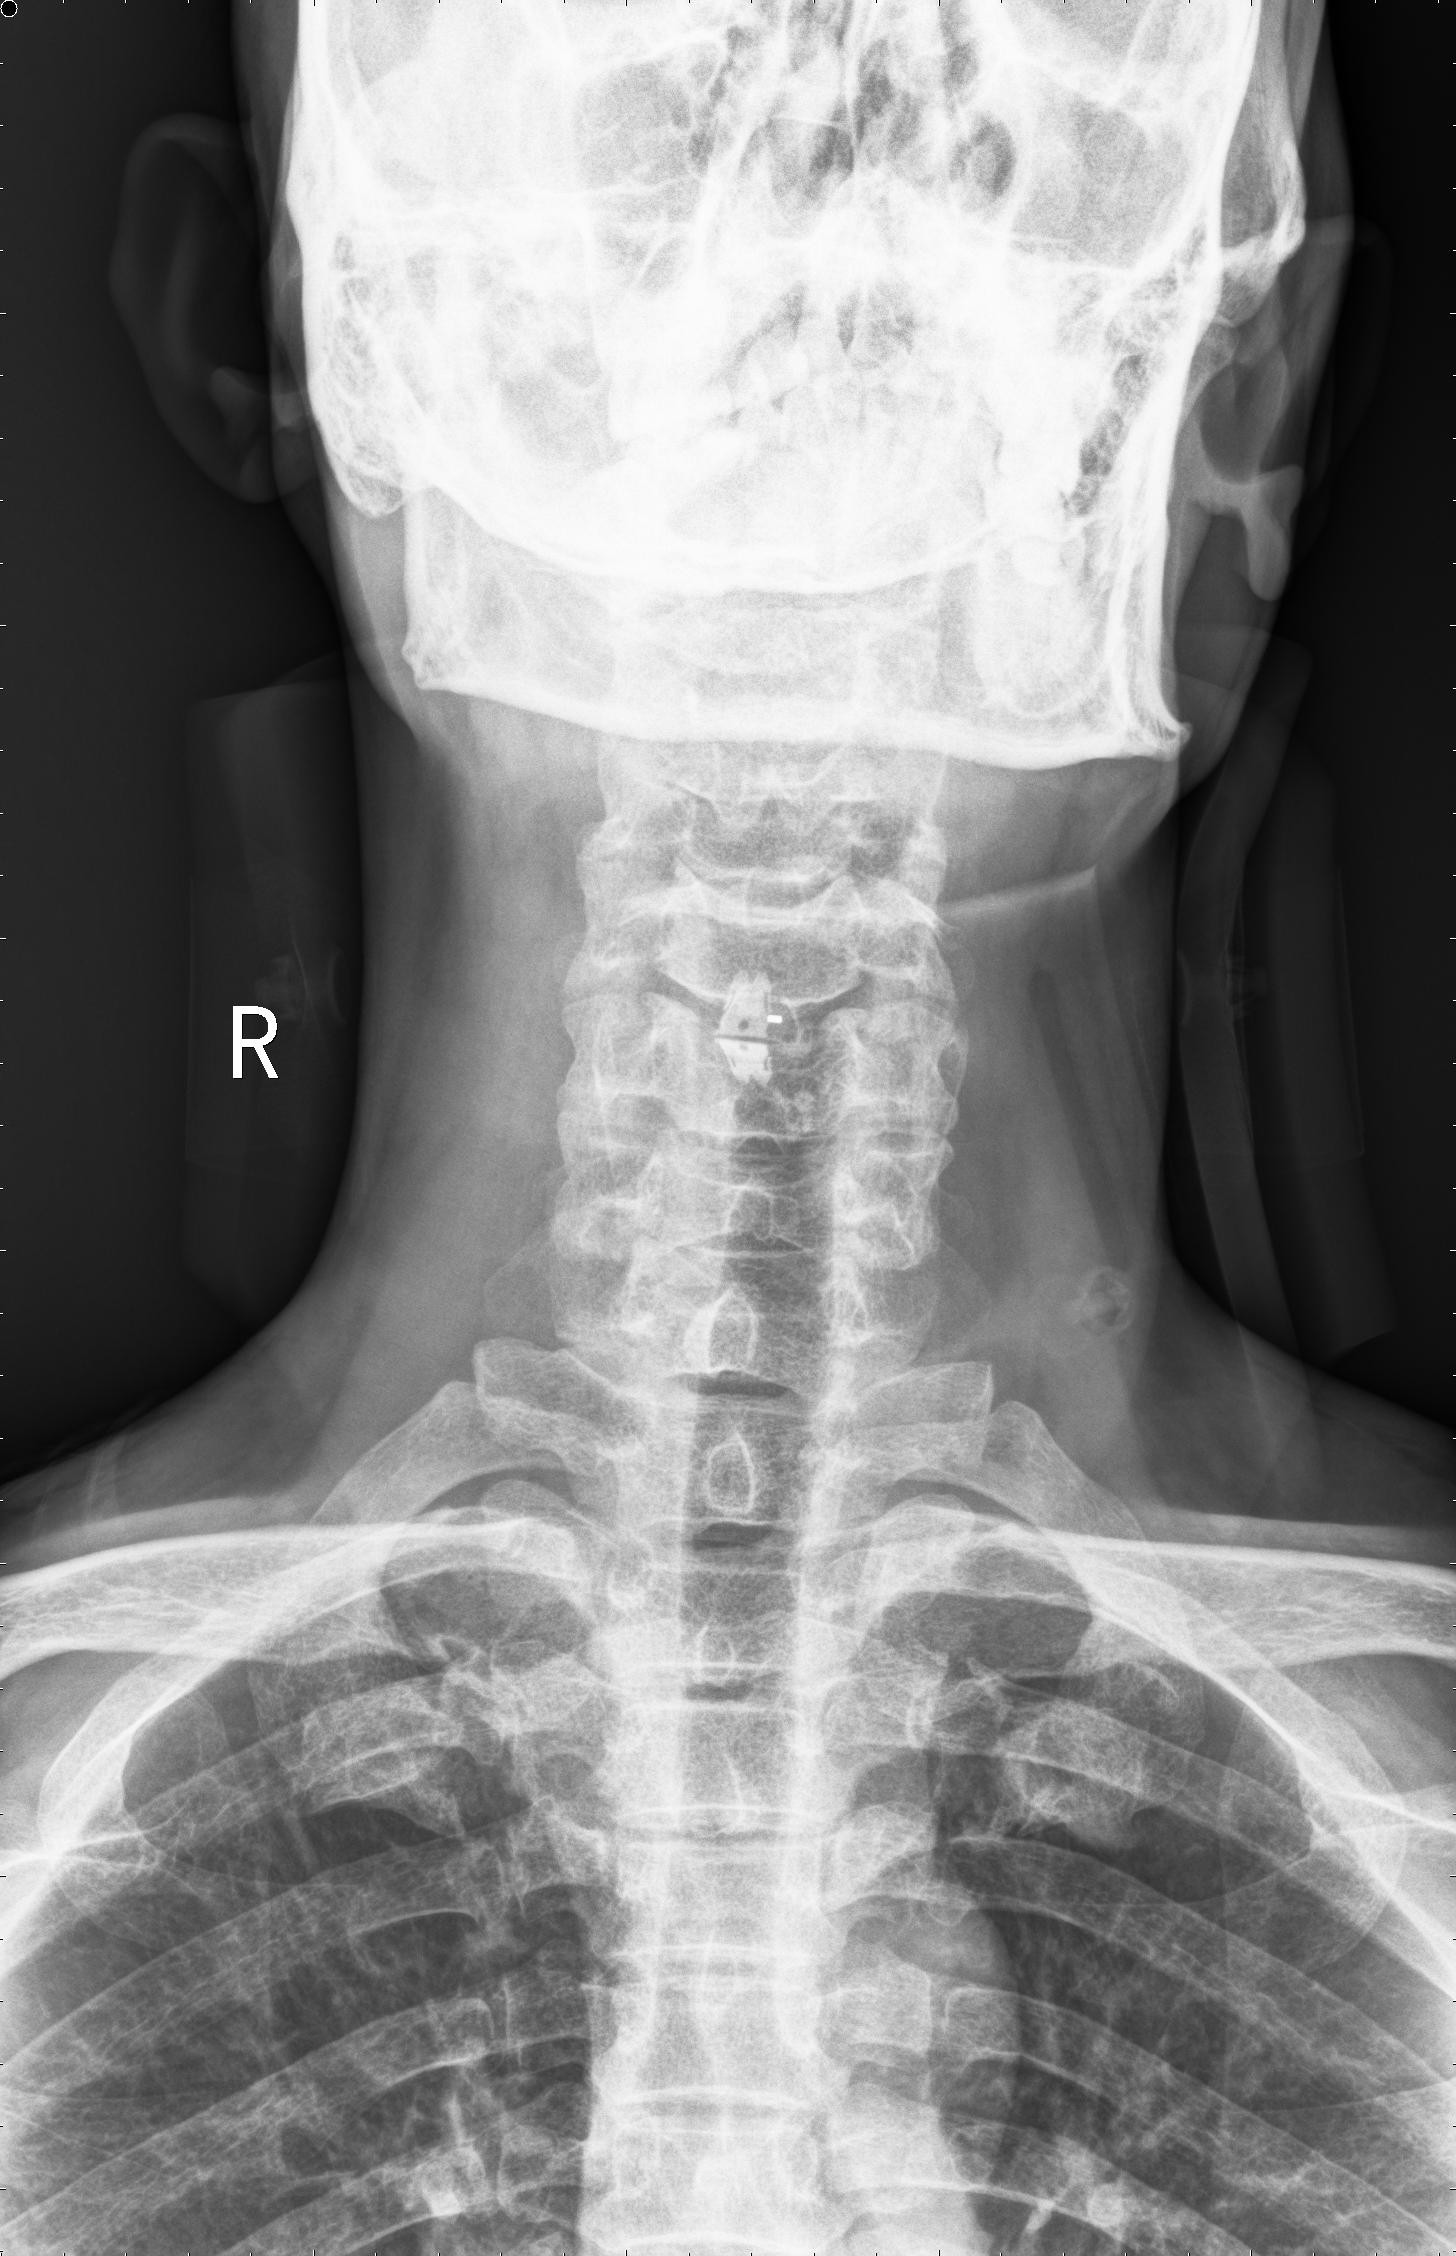

图2

图2 术后颈椎X线提示颈椎桥形锁定融合居中,椎间隙高度恢复正常,融合良好